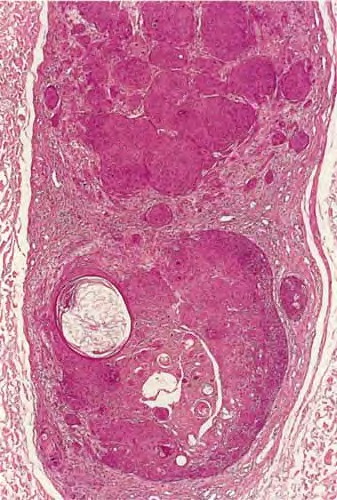

Inverted follicular keratosis = التقران الجرابي المقلوب